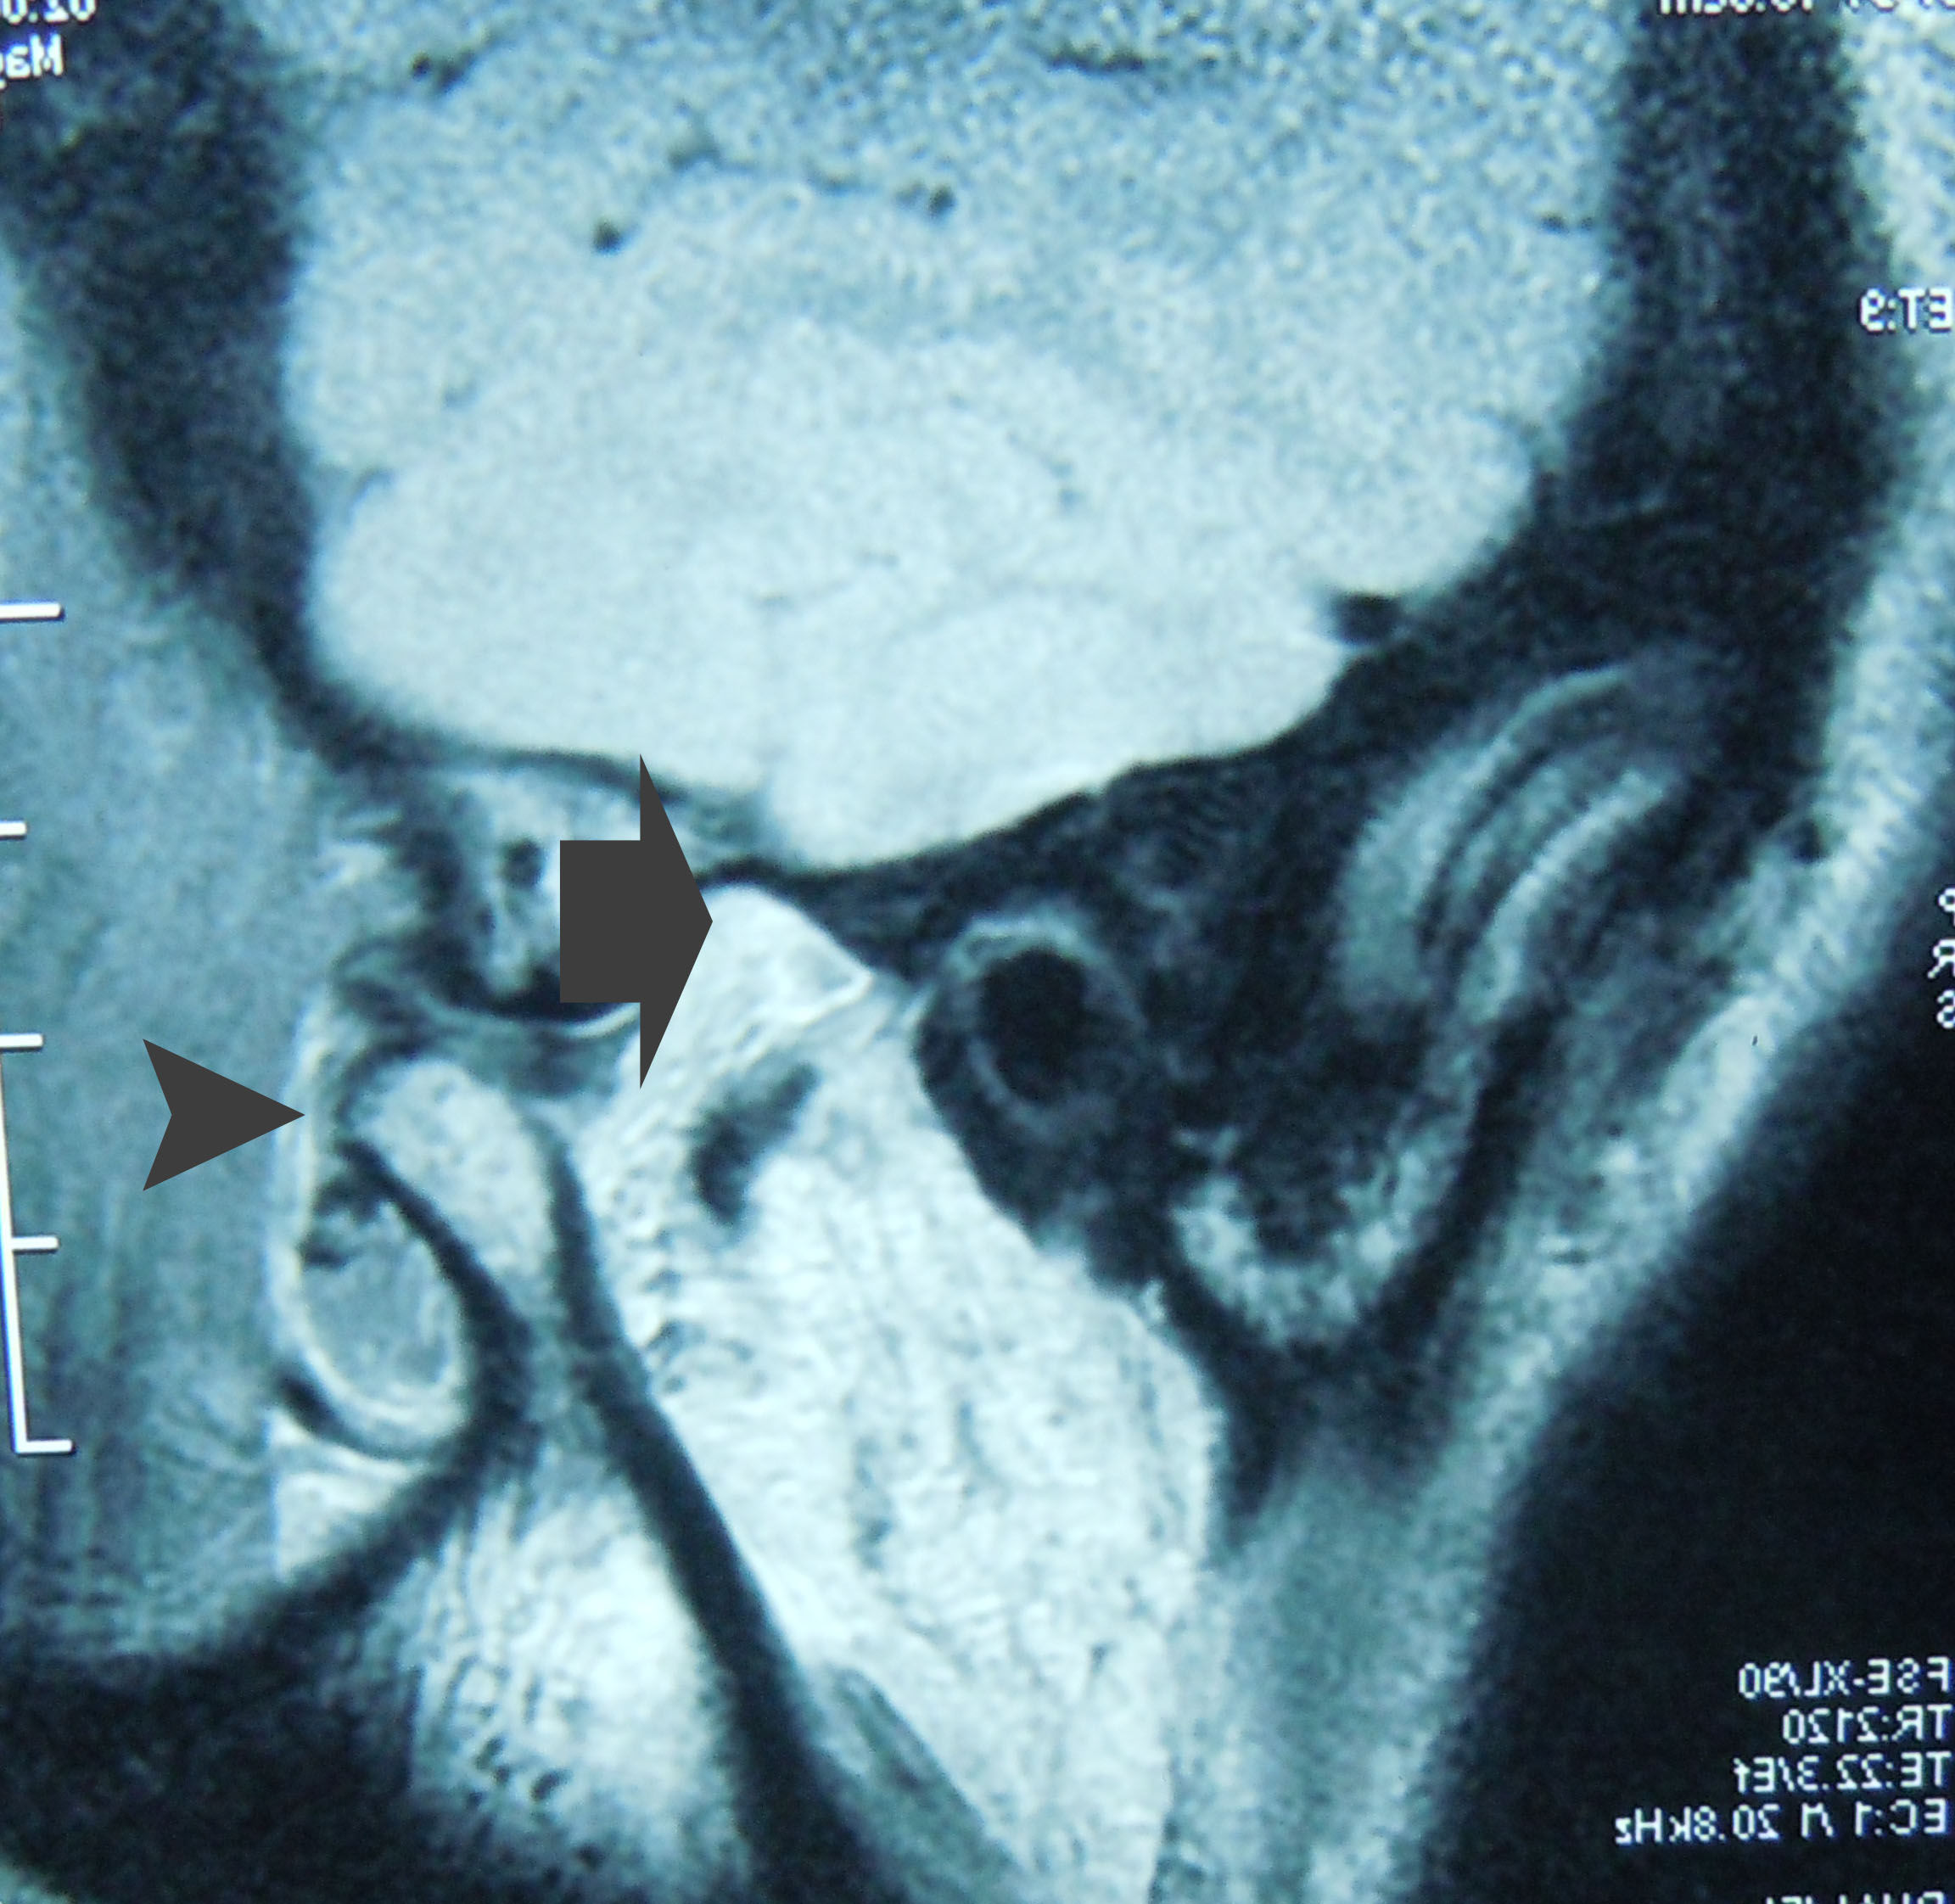

一年前患者突然出现面部偏斜,于南京就诊,南京医生说是一侧颞下颌关节的过度发育,等患者关节没有发育完成,不能手术,没能诊断出关节脱臼,这是脱臼当时的磁共振片子,片子显示颞下颌关节髁突(arrow head)明显脱离了关节窝(arrow)

颞下颌关节的髁突脱离了关节窝,卡在关节结节的前面一年,在脱臼的早期是非常疼痛的,不能合拢嘴巴,前牙咬不上。可是这个病人现在一点都不疼,牙齿能错位的咬合上,看见当初这个病人当初忍受的多少天的痛苦呀。做为医生不能想像。